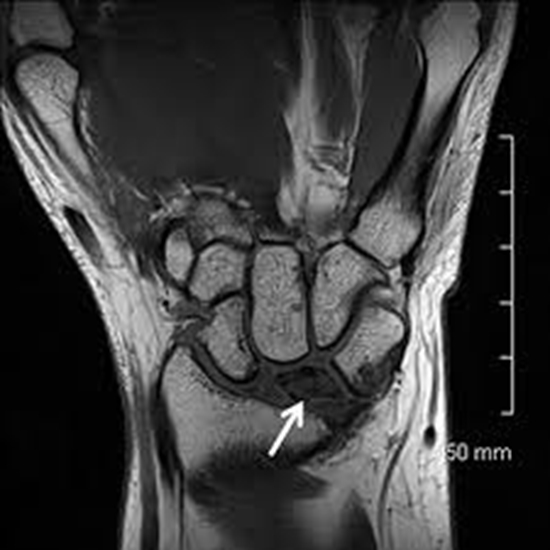

مقایسه کمی و کیفی سکانس های T2 BLADE,PD BLADE,3D T2SPACE با سکانس های روتین برای ارزیابی ضایعات مچ دست در دستگاه 3T

مقایسه کمی و کیفی سکانس های T2 BLADE,PD BLADE,3D T2SPACE با سکانس های روتین برای ارزیابی ضایعات مچ دست